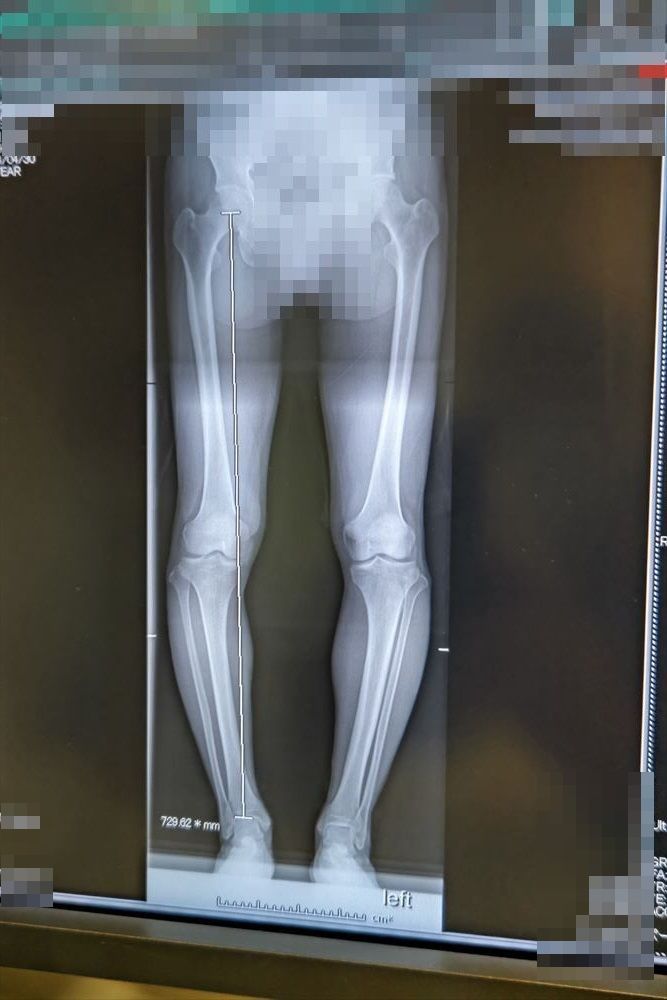

骨切りはO脚が酷いので脛の骨は2本とも切らないといけないとか。

【O脚.jpg : 63.3KB】